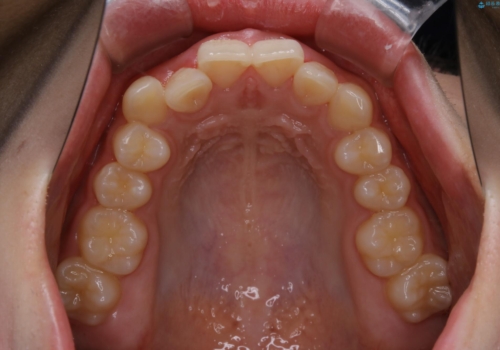

前歯のがたつきとディープバイト:インビザライン治療

- 前歯のがたつきと、噛み合わせが深いことを気にされてご相談にいらした方です。

インビザラインにて治療を行いました。

一般的に、歯冠(歯の長さ)が短い方はインビザライン治療に時間がかかりやすい傾向にあります。

歯の移動量に対して大きなブラックトライアングルもできることなく綺麗に並べることができ、大変喜んでいただけました。